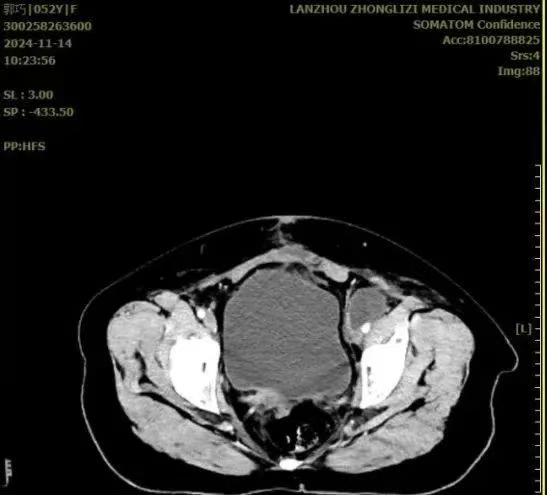

治疗前

治疗后

放疗过程顺利,复查提示病情稳定